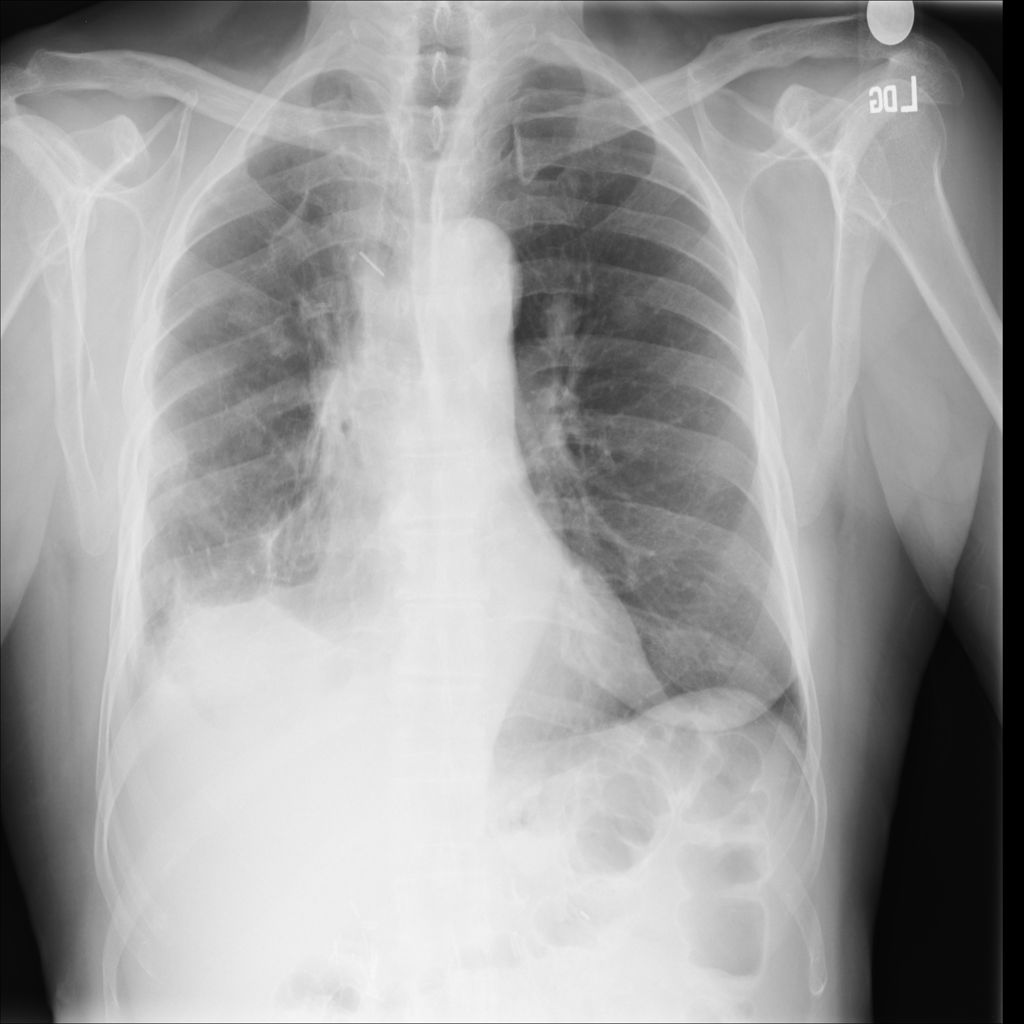

PAT-50E5 · IMG-000Nodule

PAT-50E5 · IMG-000

PA